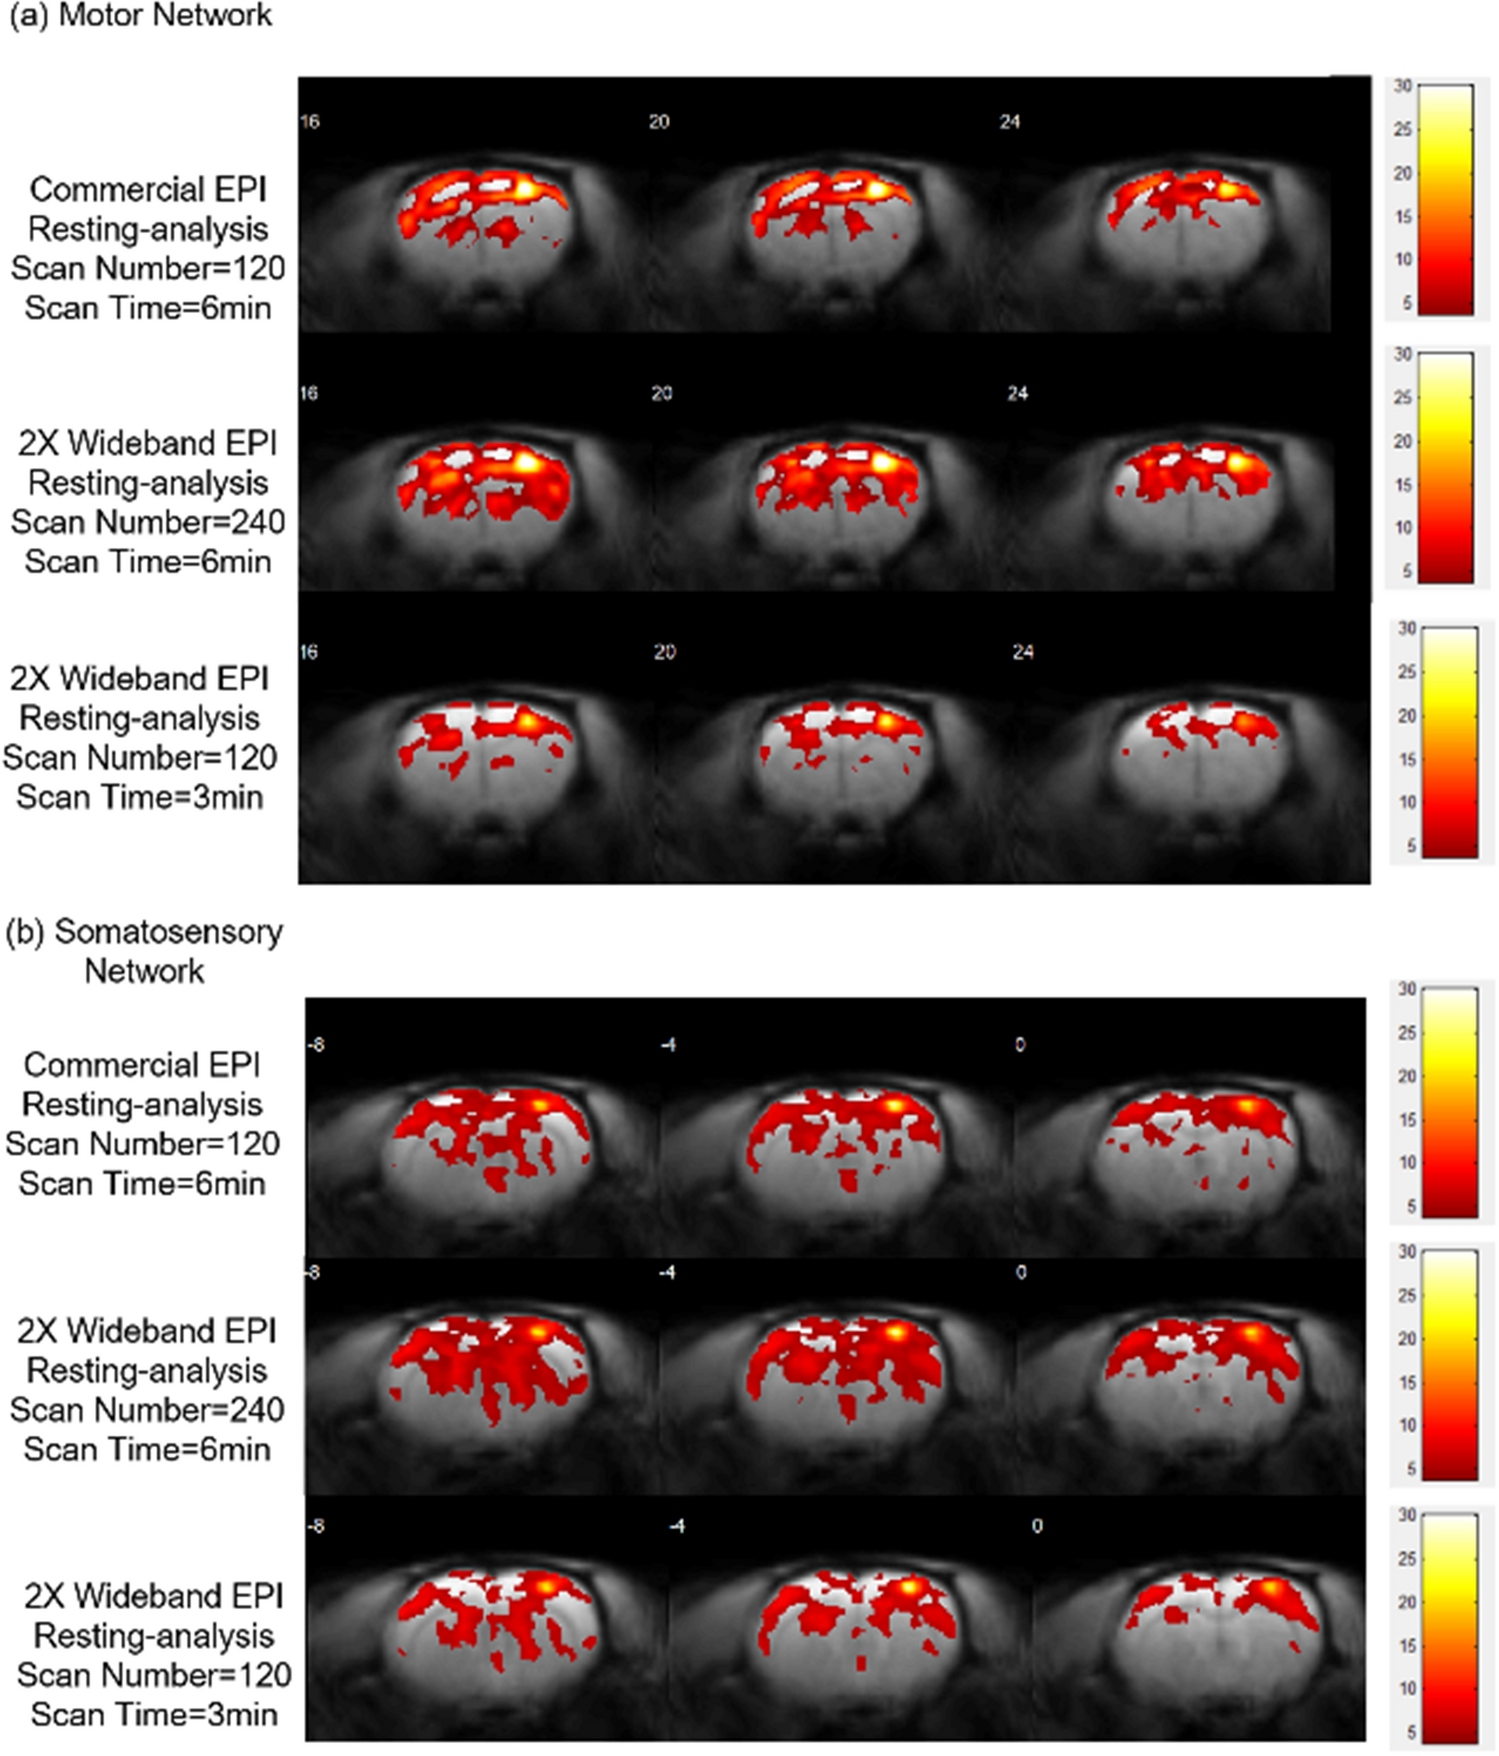

Figure 14

Resting-state functional connectivity. Resting-state functional connectivity with bandpass filtered at 0.01 and 1 Hz. Group resting-state functional connectivity maps (p < 0.005, N = 6) using seed regions in the (a) right motor network, (b) right somatosensory network. The 2X Wideband EPI (Scan Number = 240) shows increased (1.38 times as conventional scan) regional connectivity, but 2X Wideband EPI (Scan Number = 120) reveals less (0.78 times as conventional scan) connections in the right motor network. In the right somatosensory network, 2X Wideband EPI (Scan Number = 240) presents 1.34 times relative regions but 0.82 times regions are observed in 2X Wideband EPI (Scan Number = 120).